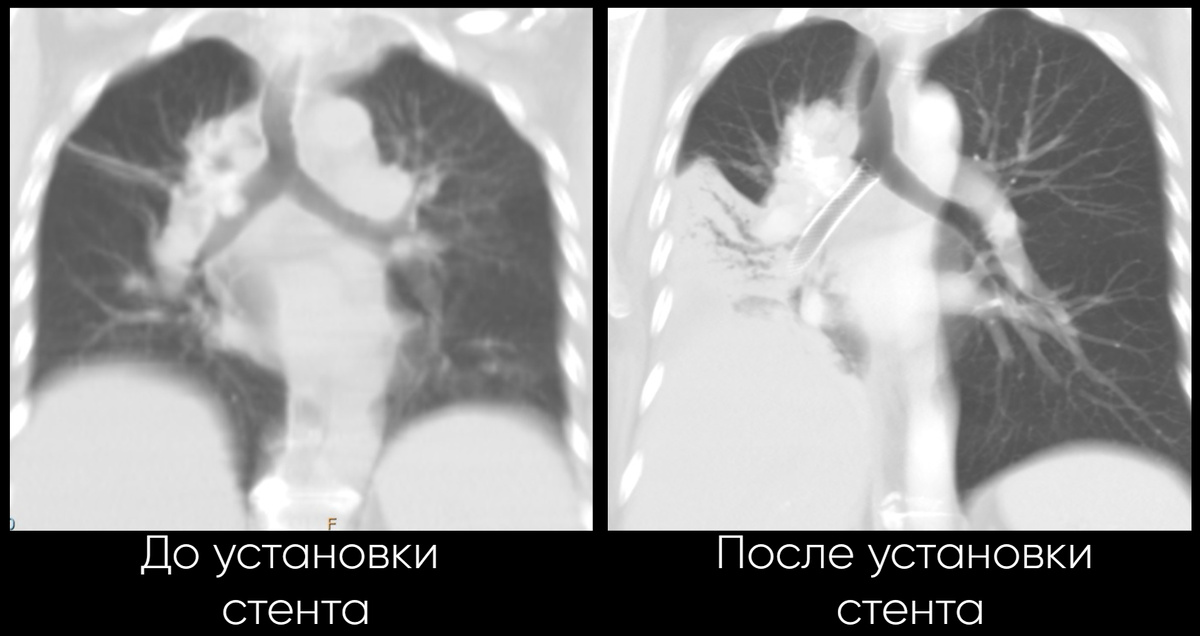

После проведения КТ у женщины выявили опухолевый стеноз трахеи и бронхов – опасное состояние, при котором растущее новообразование перекрывает дыхательные пути, лишая человека возможности дышать.

Пациентку госпитализировали в отделение торакальной онкологии. В срочном порядке было принято решение о стентировании трахеобронхиального дерева - операции, необходимой для восстановления проходимости дыхательных путей.

Благодаря высокому профессионализму и слаженной работе специалистов из разных отделений, пациентке установили стент - специальный каркас, расширяющий суженный участок дыхательных путей. Теперь женщина сможет снова дышать свободно.

Это был первый опыт стентирования трахеобронхиального дерева, проведенный в нашем диспансере, и он прошел успешно. Для пациентки, страдающей тяжелым заболеванием, это единственный шанс улучшить состояние здоровья и продлить жизнь.